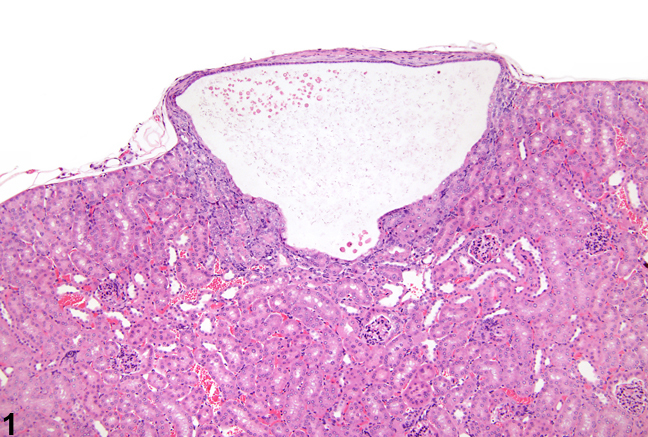

Simple renal cyst

Very common.

Dilated tubule with a low cuboidal or flattened pink epithelial lining. Usually unilocular. If multilocular, septa divind the cysts should be unremarkaable stroma with no epithelial islands or nodules.

There should be no clear cells.